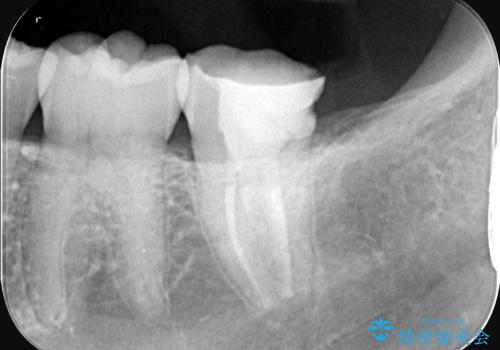

- 昨日からのズキズキとした激しい痛みを主訴にご来院されました。レントゲンおよび歯髄診察の結果、不可逆性の歯髄炎(歯の神経の重度の炎症)と診断。歯を残すことを第一に、まず痛みの原因である神経を取り除く根管治療を提案しました。また、虫歯が歯肉の下まで深く進行していたため、根管治療後に歯周外科処置を行い、最終的に精密なセラミッククラウンで修復する、総合的な治療計画を立案しました。

治療はまず、根管治療から始め、感染した神経を徹底的に除去することで、痛みをすぐに解消しました。再発を防ぐため、ラバーダムや顕微鏡を使って、根管内を丁寧に、そして精密に処置しました。次に、深い部分の虫歯を確実に治療するため、歯周外科処置を行い、治療しやすい環境を整えました。最後に、機能と見た目に優れたセラミッククラウンを作製・装着。根管治療から外科処置、審美修復までを一貫して行うことで、再発リスクの低い、長期的に安定して使える奥歯を取り戻していただけました。